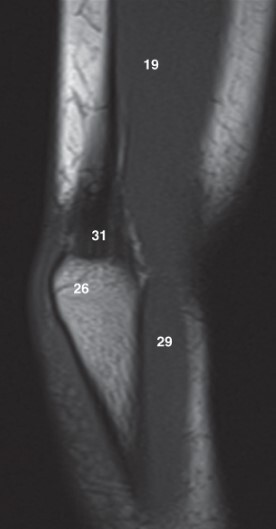

Label 19 and 26

19-Lt. Triceps brachii muscle

26-Olecranon process of lt. ulna